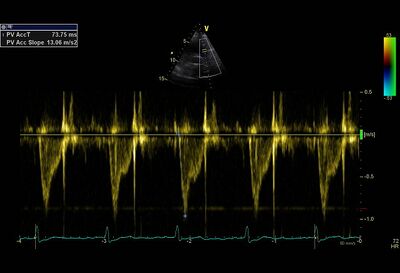

| AccT

>120 ms

120-60 ms

<60 ms

Calculations for estimating pressure in the pulmonary artery

| Mean PA pressure

| 90 - (0.62 x ACCT) if Acct < 120ms

Examples of severe pulmonary hypertension1

| Short AccT with "systolic notch"